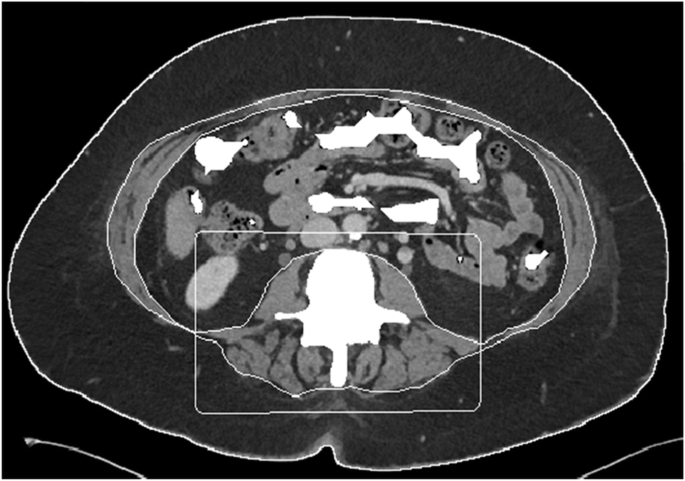

Body composition measurements

Example of segmentation of a computed tomography image with boundary lines between external air and subcutaneous fat (1), between subcutaneous fat and abdominal wall/paraspinal muscles (2), and between abdominal wall/paraspinal muscles and visceral fat (3). The box around the paraspinal muscles allows the algorithm to separately calculate the paraspinal muscle area (if this information is desired)